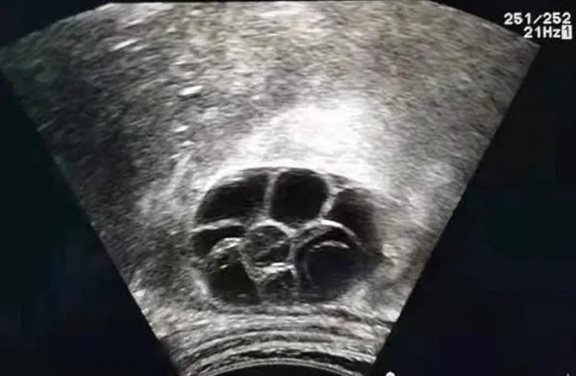

巨大子宫占据盆腔

腹部超声下右侧卵巢在肋下缘